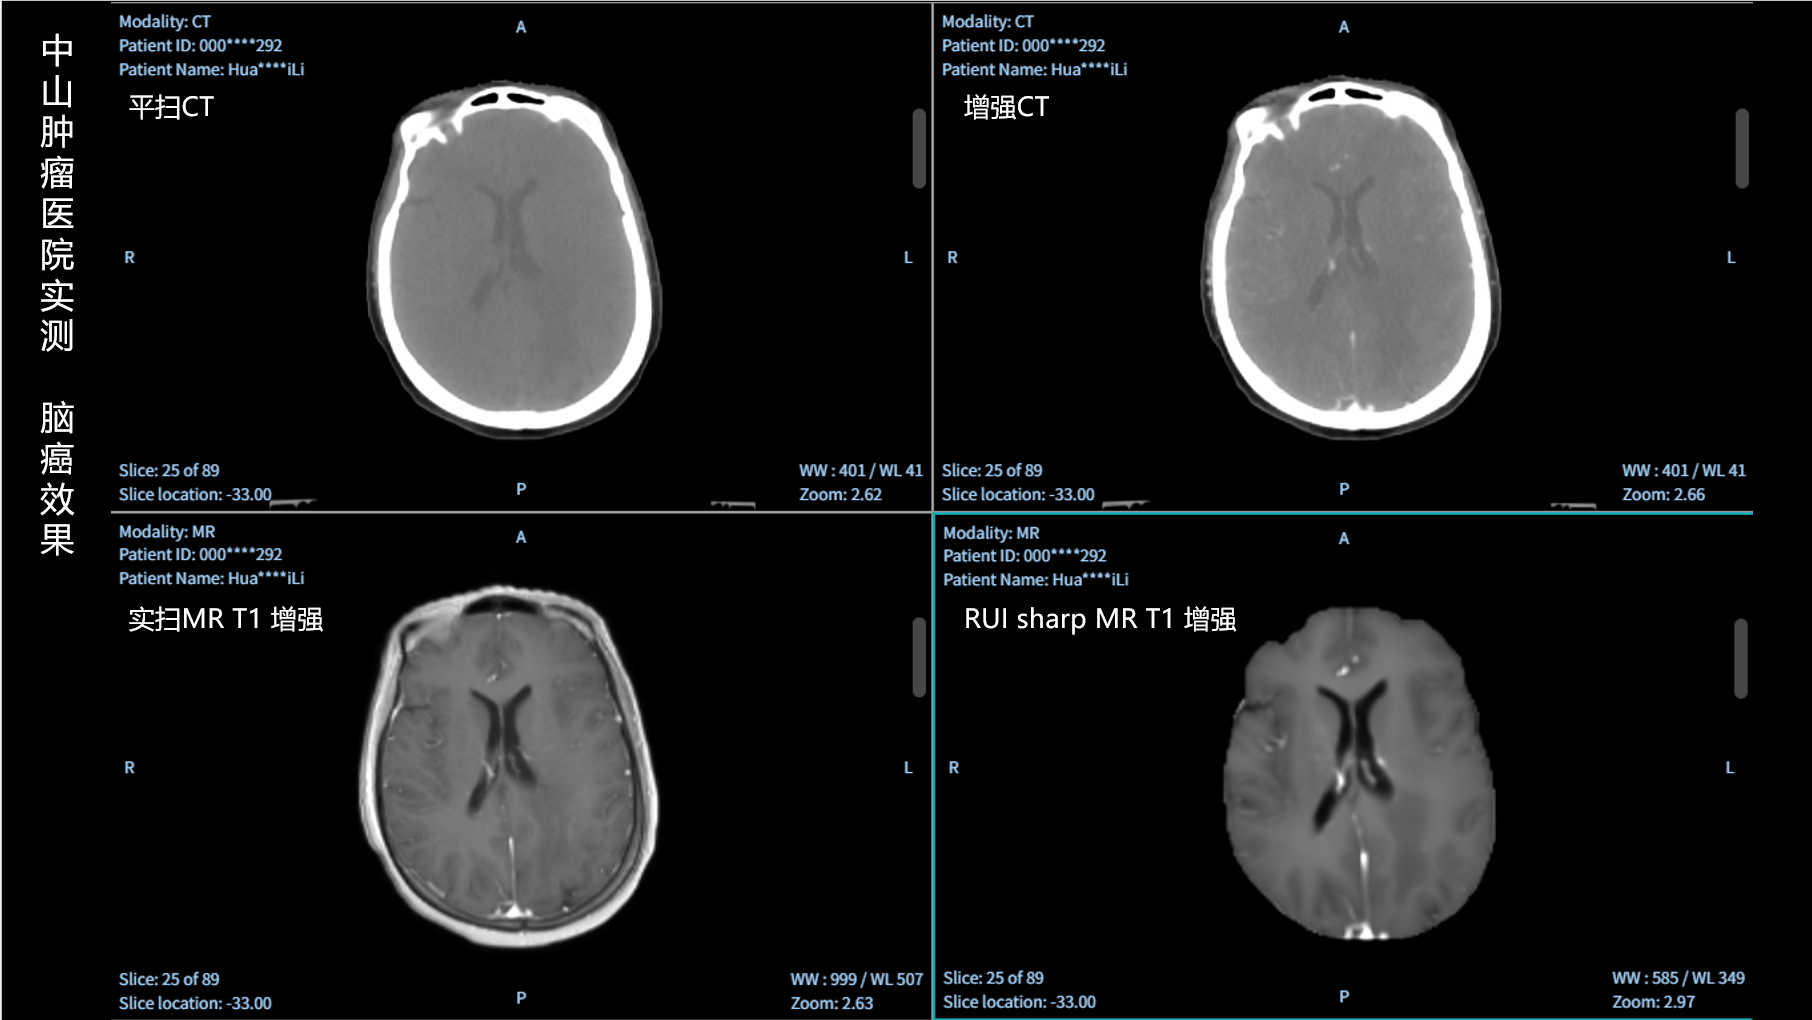

RUI sharp H(锐影)可在不依赖MRI的前提下,显著提升头部CT图像的软组织分辨率,为临床提供更高质量的辅助信息,尤其适用于MRI资源受限或较难配准的头颈部放疗感兴趣区勾画场景。

可大幅提高头部CT影像软组织分辨率,使肿瘤和周边器官显示更清晰,为放疗靶区勾画提供参考。

无需图像配准,CT和锐影图像同源,可匹配、叠加、"淡入淡出"显示。

实测效果